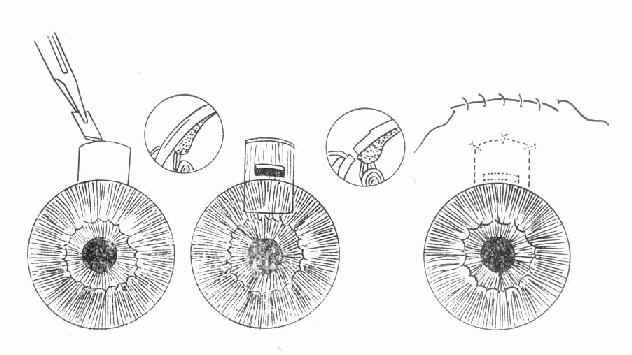

急性闭角型青光眼虽可用药物治疗使急性发作缓解,达到短期降压的目的,但不能防止再发。因此眼压下降后应根据病情,特别是前房角情况,尽快选择周边虹膜切除术或滤过性手术(图10-4)。

图10-3 闭角青光眼虹膜切除术后

(前房加深,房水经周边虹膜切除口进入前房)

图10-4 周边虹膜切除术

若停药48小时眼压不回升,房角功能性小梁网1/2以上开放以及青光眼临床前期,可施行周边虹膜切除术。对于眼压控制不到正常范围,房角已发生广泛前粘连者,应考虑作滤过性手术或小梁切除术。(图10-5)。

图10-5 小梁切除术